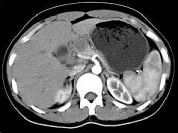

- 单项选择题结合图像,最可能的诊断为 ( )

A、胰腺癌

B、胰岛细胞癌

C、胰腺囊腺癌

D、胰腺炎

E、以上都不是